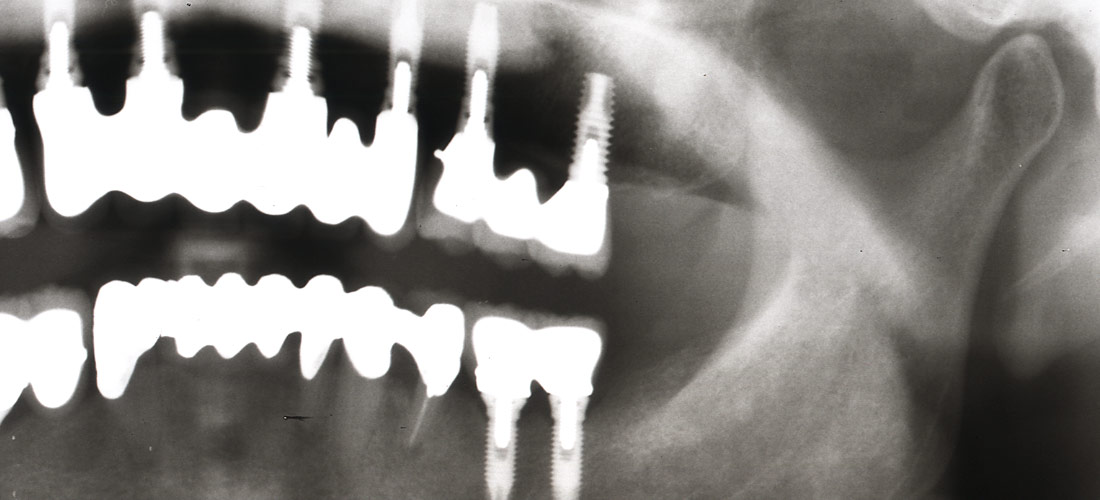

複雑なインプラント治療

インプラント治療